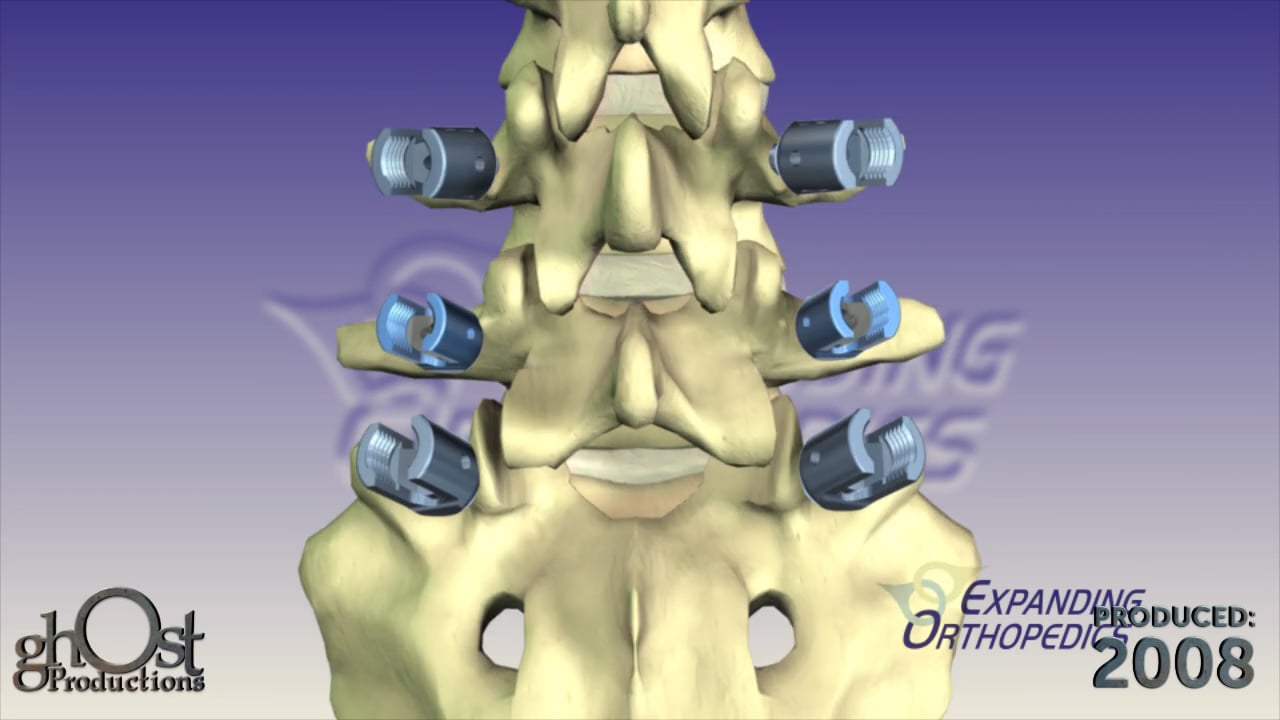

Expanding Orthopedics partners with Ghost Productions to create an animation showcasing their VCF posterior lumbar fixation system for spinal stabilization.

Expanding Orthopedics has collaborated with Ghost Productions to create an informative animation showcasing their VCF posterior lumbar fixation system. This innovative device is designed to stabilize spinal motion and promote interbody bone fusion in patients suffering from vertebral compression fractures. The animation demonstrates how the threaded interbody fusion cage is inserted into the lumbar disc space and used in conjunction with standard pedicle screws to provide optimal support and healing. This video is a valuable resource for medical professionals seeking to learn more about this cutting-edge technology in the field of orthopedics.

Expanding Orthopedics, Ghost Productions, VCF posterior lumbar fixation system, spinal motion stabilization, interbody bone fusion, vertebral compression fractures, threaded interbody fusion cage, lumbar disc space, pedicle screws, optimal support, healing, medical professionals, cutting-edge technology, orthopedics.